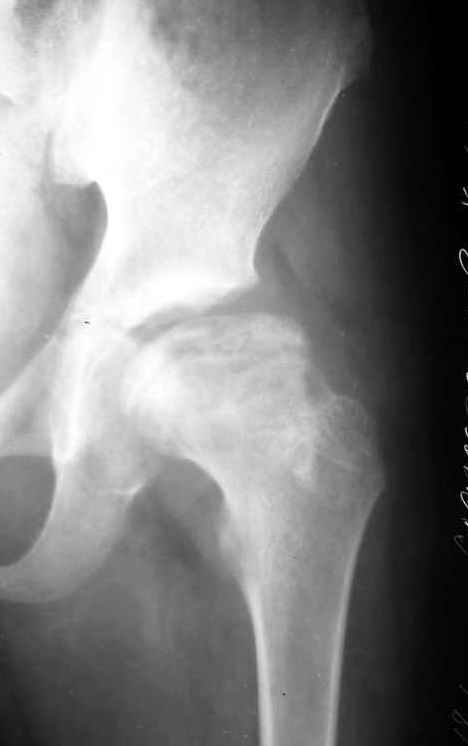

Мальчик 12 лет. Год назад по поводу асептического некроза, в субкапитальную область пересадил аутокостный трансплантат, взятый из Spina iliaca an.sup., на мышечной ножке m.sartorius.

На представленной рентгенограмме (лев. сустав) типичная картина последствия болезни Пертеса с уменьшенной высотой эпифиза. Процесс завершился и нет необходимости в дальнейшем использовании доп. средств опоры. Выраженных дспластических явлений нет. Позвольте пациенту жить без особых ограничений, но ежегодно проводите контрольный осмотр. АИФ.